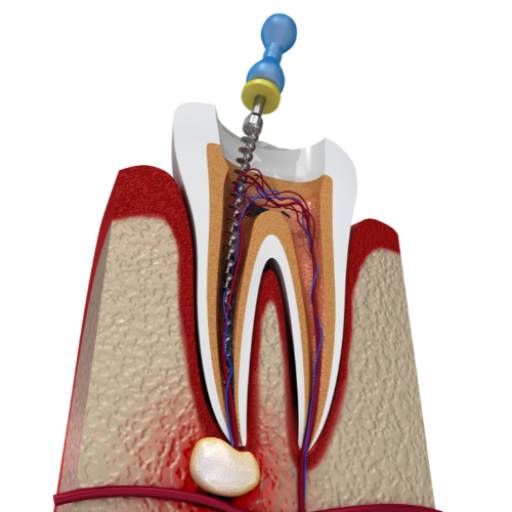

- Endodontia: Tratamento especializado de canal dentário, preservando dentes comprometidos.